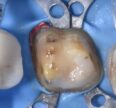

Class II biomimetic composite restorations

#GC #Prototype #ClassIIcavities